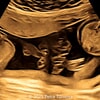

A 33-year-old nullipara with non-contributory medical history presented at 20 weeks, 6 days based on an early scan. Ultrasound revealed the following findings. There were no other apparent abnormalities. What is the most probable diagnosis?